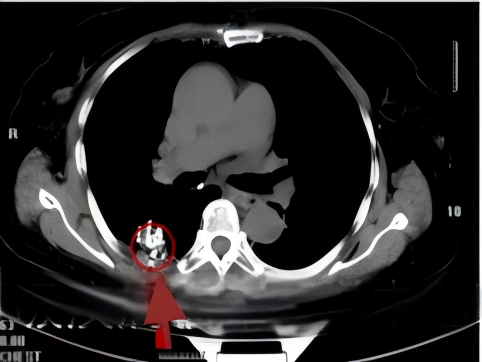

患者王先生(化名),因长期咳嗽、胸闷、气促前往我院呼吸与危重症医学科就诊,查胸部CT后,见到左主支气管下端完全阻塞,并伴有胸腔积液,考虑肺癌;随后呼吸与危重症医学科专家团队为患者实施经支气管镜检查,发现患者左主支气管壁存在肿瘤组织,病理报告显示肺鳞癌,最终在科室专家严格的诊断下,确诊为:左肺鳞癌IIIB期(中晚期)。

考虑患者自身情况,经科室专家团队严谨的讨论评估,若进行外科手术将切除全肺,患者生活质量将大幅下降,在充分征求患者及家属意见并同意后,科室为患者制定了放射性粒子植入治疗的方案并实施治疗。治疗三周后,复查支气管镜,患者左支气管通畅,治疗一月后,病灶稳定并呈现缩小的趋势。